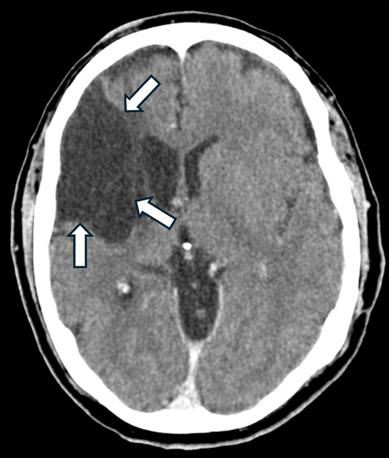

Puede producir trombos que van del corazón hacia cualquier parte del organismo, dentro de los desenlaces más

catastróficos se encuentran los infartos cerebrales los pueden ser muy graves y de un momento a otro cambiar dramáticamente la vida del enfermo, de ser una persona funcional a ser una persona incapacitada de por vida